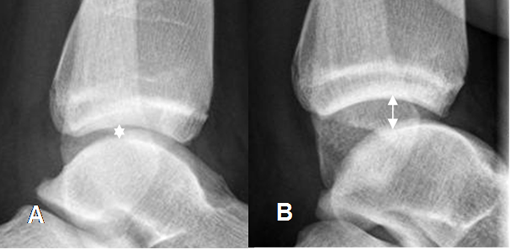

En casos de lesión de la sindesmosis tibioperoneoastragalina, se produce ruptura de los ligamentos interóseos (Tibioperoneo anterior y posterior). En la Rx se observa aumento del espacio entre la tibia y el peroné mayor de 6 mm, en la proyección AP. (12). (Fig 59 A y 59 B). En las Rx de stress puede haber aumento de los espacios articulares, en casos de lesiones ligamentarias completas. (Fig 59 C y 59 D).

Fig 59. Lesión de ligamentos de la mortaja tibioperonea.

A: Rx AP. Aumento del espacio tibioperoneo, por lesión ligamentaria.

B: TAC axial. Aumento del espacio tibioperoneo posterior, por lesión ligamentaria.

Fig 59 B. Lesión de la mortaja.

A: Rx AP. Fractura no desplazada del peroné distal. Se aprecia incremento del espacio articular tibio peroneo distal y subluxación de la articulación tibioastragalina, por lesión ligamentaria.

B: Rx AP. Cambios PostQx con reducción de la subluxación y estabilización de la fractura en el peroné.